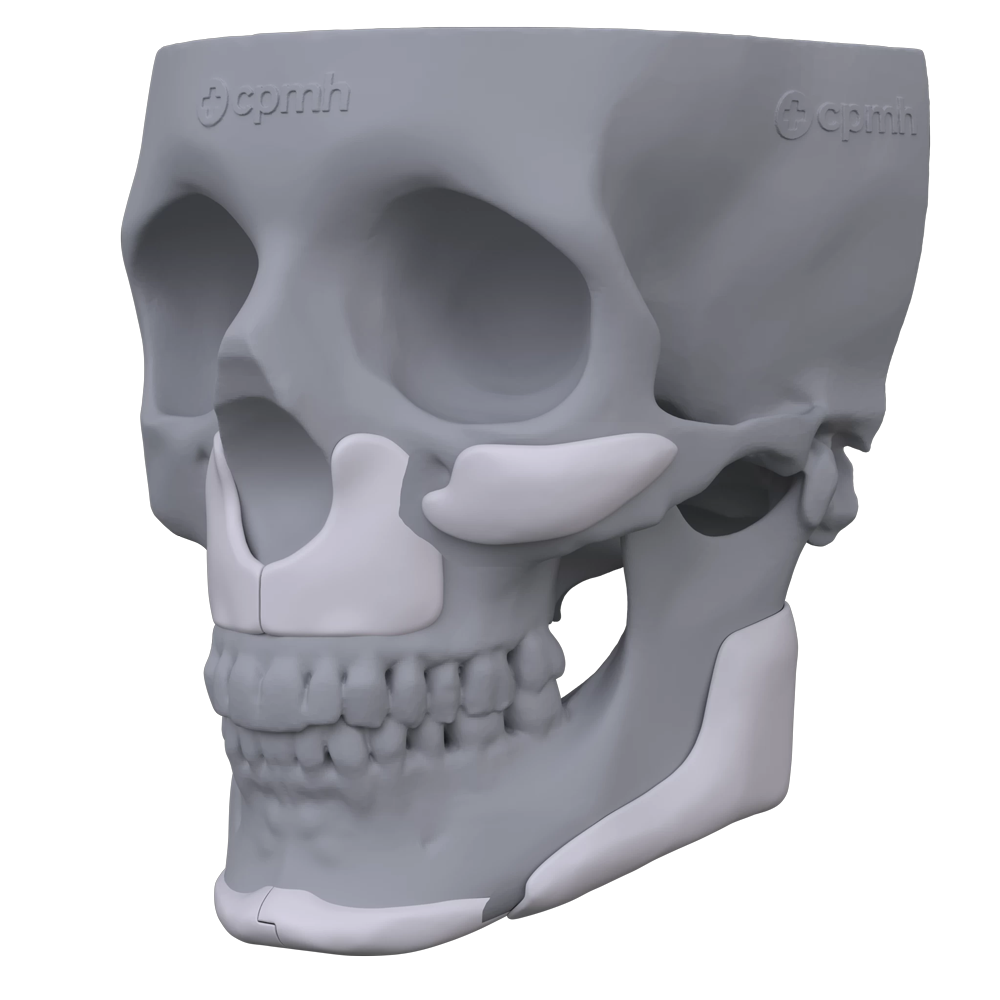

Tipos de próteses faciais

As opções trazidas pelo planejamento 3D, com as possibilidades do paralelismo facial, se associam ao uso do PMMA como ferramentas poderosas para potencializar os resultados nos pacientes.

São próteses personalizadas fabricadas especificamente para cada caso

Planejamento virtual milimétrico e detalhado para visualizar o resultado da cirurgia

Fabricação personalizada das próteses